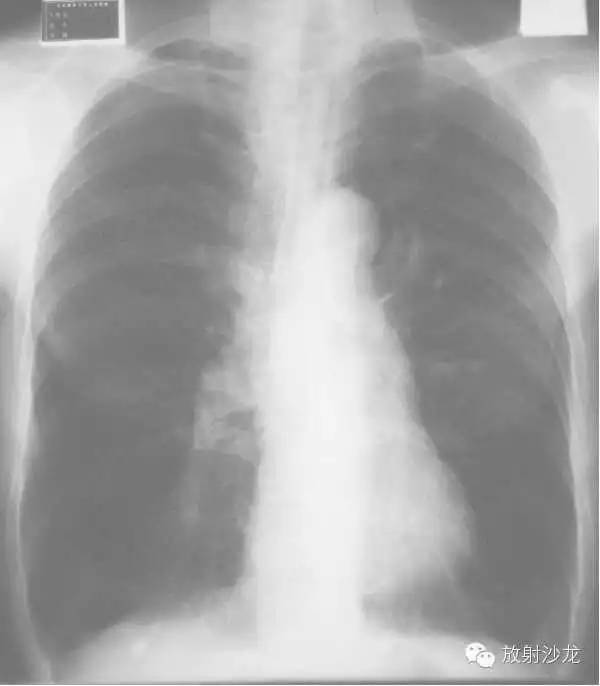

心包炎(pericarditis)

1、心脏向两侧增大,正常心缘弧度消失。

2、腔静脉增宽(体静脉回流右房受阻)。

3、心脏血管比率增大,主动脉影缩短。

4、心缘搏动下降,主动脉搏动正常。

5、肺纹理减少或正常(右心排血量减少)。

6、造影:各心腔无扩张,腔静脉扩张。